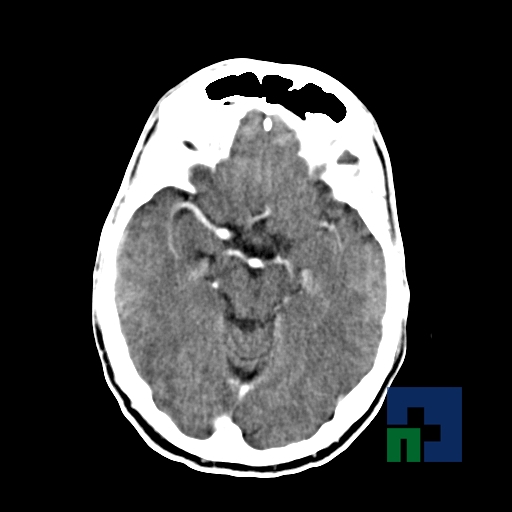

Examinare de rutină cerebrală, nativ și cu substanță de contrast (SDC) pentru diagnosticul:

- Accidentelor vasculare cerebrale ischemice sau hemoragice

În cazul traumatismelor cranio-cerebrale:

- Evaluarea deplasării liniei mediane

- Evaluarea cisternelor perimezencefalice

- Diagnosticul edemului cerebral, a contuziei cerebrale, a leziunilor axonale difuze edematoase/hemoragice, a dilacerării cerebrale, a hematomului intraparenchimatos posttraumatic, a hematoamelor subdurale/extradurale (acute, subacute, cronice), a hemoragiei intraventriculare, a hemoragiei subarahnoidiene